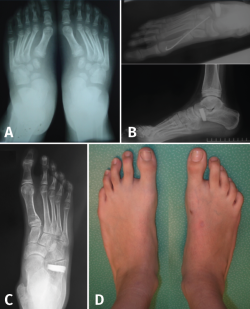

Pie en serpentina (skewfoot)

El pie en serpentina o en Z constituye una deformidad rara en el pie, que combina valgo del retropié con aducción del antepié (Figura 18).

Figura 18. Pies en serpentina. A: radiografía dorsoplantar de la deformidad en serpentina; B: imágenes radiológicas postoperatorias inmediatas, donde se aprecia osteotomía de Mosca y técnica de Cahuzac percutánea; C y D: imagen clínica y radiológica un año tras la intervención.

A menudo infradiagnosticado, suele presentarse como un metatarso aducto resistente al tratamiento. En la radiografía se manifiesta con signos de valgo del retropié con divergencia AC aumentada y aducción del antepié al nivel de la articulación de Lisfranc.

En caso de indicación quirúrgica se debe corregir el doble componente de la Z con osteotomía de alargamiento de la columna externa (para corregir el valgo) más corrección del antepié mediante técnica de Cahuzac (apertura de la cápsula C1M y osteotomía de los metatarsianos centrales) modificada en percutánea(20).